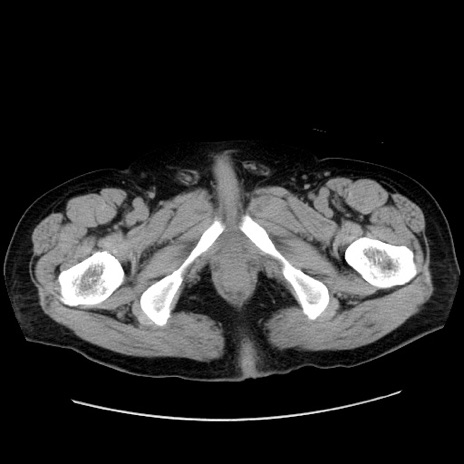

症例30(横断像)

【症例】80歳代男性

【主訴】臍周囲痛

【現病歴】約6時間前から臍下部痛が出現。次第に腹部膨隆・背部痛も生じてきたため来院。背部痛の場所は変化しない。

【既往歴】腎盂腎炎

【身体所見】意識清明、BT 36.3℃、BP  131/87mmHg、P 87bpm、SpO2 100%(RA)、臍周囲自発痛・圧痛あり、反跳痛なし、自発痛部位に一致して板状硬あり、腹部膨隆、腸雑音減弱、CVA tenderness両側陰性。

【データ】WBC 19600、CRP 0.33